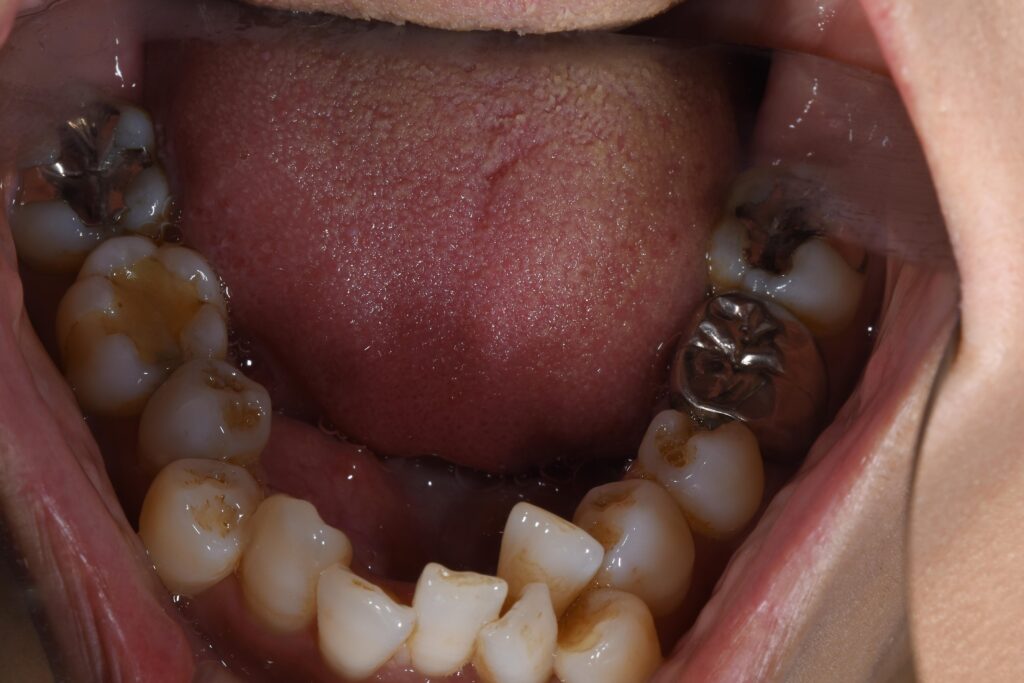

まずは矯正開始前の状態です。

写真が暗くて申し訳ございません。

【矯正開始前】

この患者様の問題点を以下に列挙します。

【問題点】

①歯のががたつきが強く、清掃困難な状態である。

②かみ合わせに問題があり、左上5番目の歯が歯周病で保存困難となったため、抜歯が必要となった。

③歯を並べるスペースが窮屈であり、スペース獲得のため便宜的な抜歯治療が必要である。

大まかに上記3点となります。

今回のように、下の歯のがたつきが顕著な場合、インビザライン(マウスピース)のみで歯並びを改善するよりも、針金を併用する治療も治療計画として考えましたが、患者様ご希望にて、針金は一切使用せず、インビザラインのみで矯正治療を行うこことなりました。